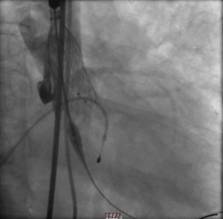

经过周密的筹备,3月5日上午,何贵新主任团队在广东省心血管病研究所罗建方教授团队的指导下,“临时起搏器植入、鞘管植入、跨瓣、球囊扩张、精准定位、瓣膜释放.......”,历经1小时余,顺利为韦奶奶行经导管主动脉瓣置换术(TAVR),置入新的主动脉瓣,打开心脏血液流出的第一道门,手术创口仅针眼大小。术后,复查超声心动图提示人工主动脉瓣膜工作良好,心脏血液泵出顺畅,术前跨瓣压差62 mmHg术后降至差2mmHg,手术非常成功,术后第2天即可下床活动。

另外一例患者谢爷爷面对一场惊心动魄的“生死战”。首先,在球囊抵达主动脉瓣口,刚准备扩开为瓣膜植入创造条件时,瞬间出现室颤,心跳骤停。“快,除颤、心肺复苏!”团队医护人员迅速抢救,同时另一组人将瓣膜送入心脏,跨瓣压差由术前127mmHg降至术后3mmHg。术后送入ICU治疗,第3天,谢爷爷病情稳定,即可下床活动。